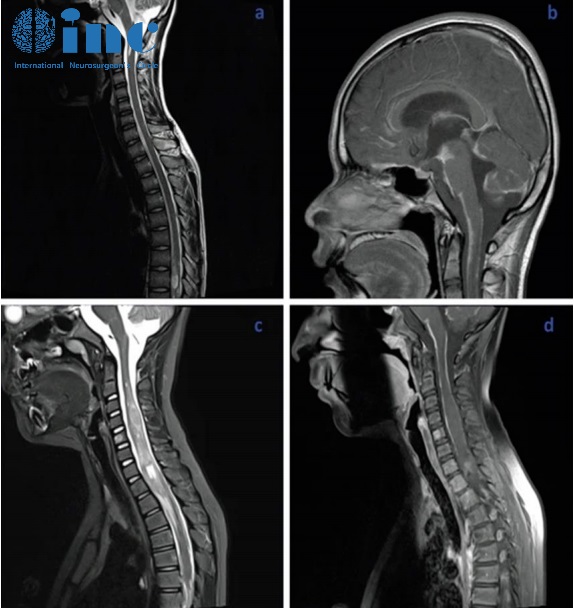

脊柱磁共振显示脑膜弥漫性强化,脑膜覆盖多处结节性病变,以及实质内病变和结节性小囊肿。

颅脑磁共振序列可见脑膜明显强化,是脑干腹侧表面上的软脑膜。

小脑弥漫性可见多发囊性病变,特别是上叶正中区和上蚓部,可能导致脑脊液循环障碍伴继发性脑室扩张。

从文献中提取的一些图像说明了刚才提到的情况:增强的蛛网膜的病理性增粗,肿瘤的多个结节状定位,相关的脑积水。大脑的非强化局灶性囊性病变是由血管周围间隙的局灶性扩大造成的,也是因为脑脊液循环受阻而扩大。

基于临床的资料(年龄、性别、非不同性的神经表现、脑积水)和神经放射学影像(特征性的颅内和椎管内结节性脑胶质增粗和强化,常伴有小囊性的非强化病变,蛛网膜下腔和室管膜表面的涂层),我可以确认弥漫性软脑膜胶质神经元肿瘤的诊断。